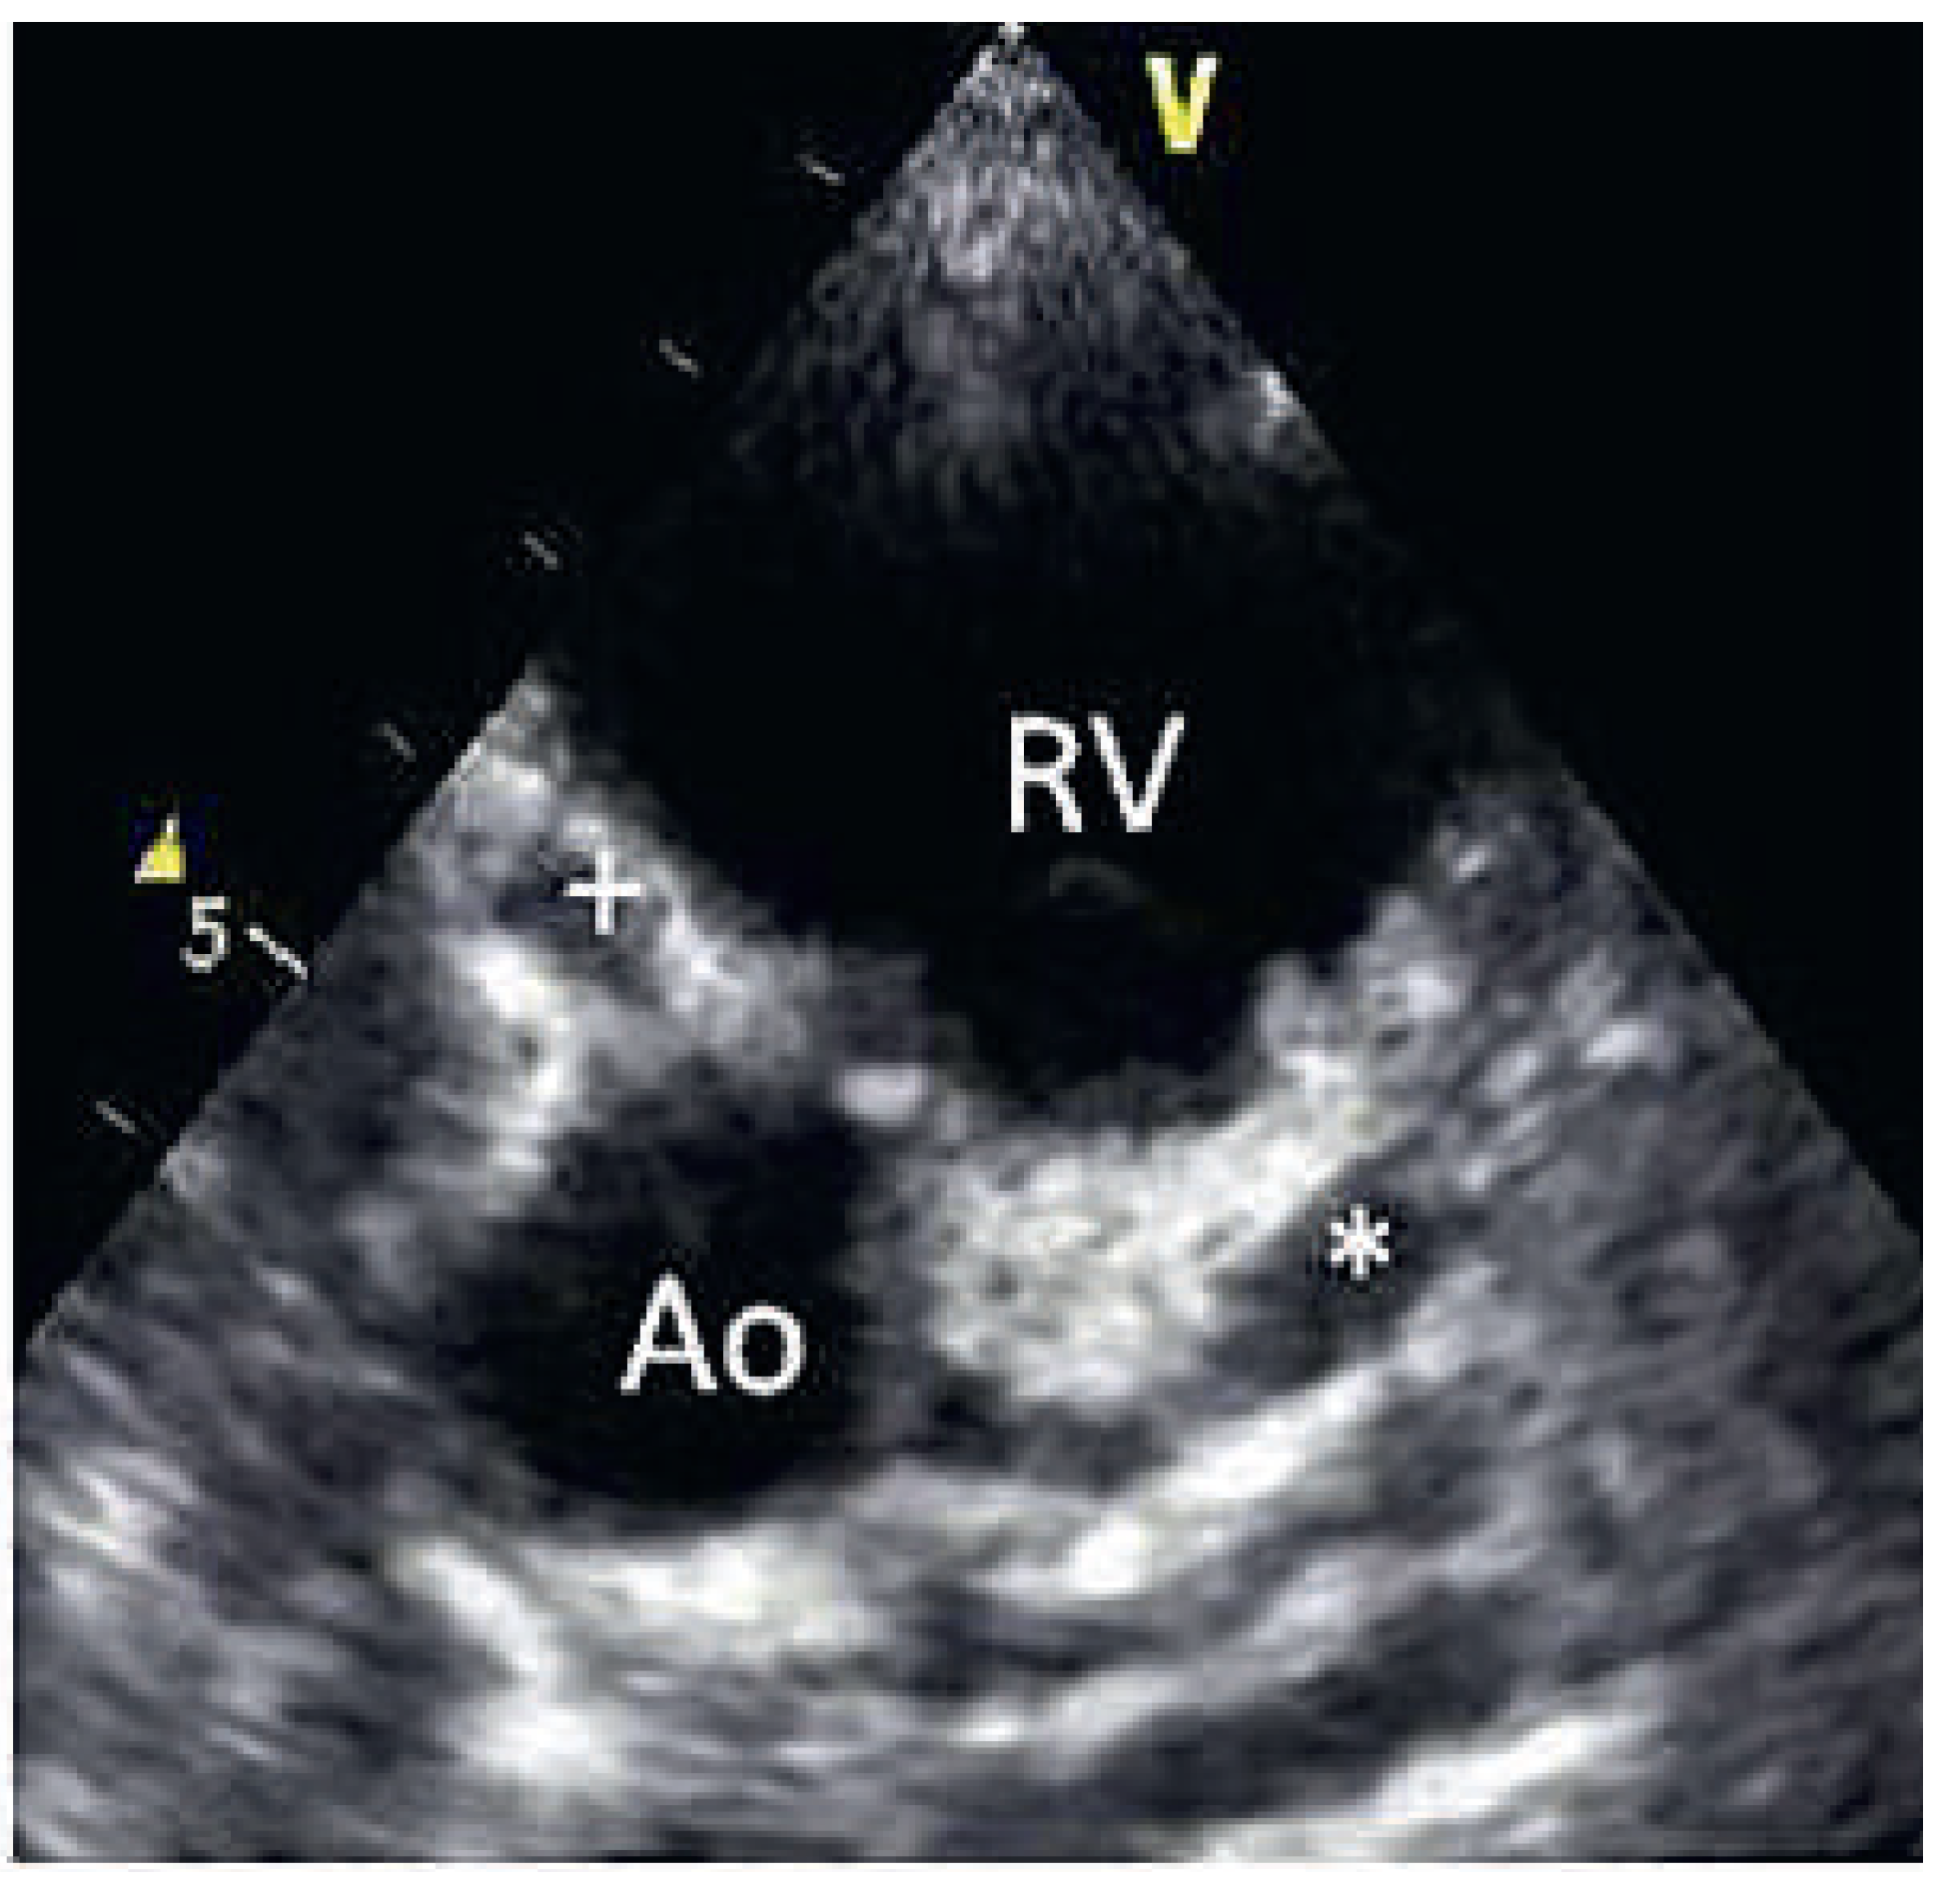

On the tenth day, we performed transthoracic echocardiography (Figure 1 and Figure 2), which revealed normal biventricular size and function, without hypokinesia. There was no pericardial effusion, no valvular disease, but a proximal enlargement of the left anterior descending coronary artery (LAD) was visualised. On the same day, because all these elements suggested Kawasaki disease (KD), treatment with intravenous polyvalent immunoglobulin (IVIG 2 g/kg as a single infusion: Privigen 70 g) and high-dose aspirin (80 to 100 mg/kg/d: 750 mg four times a day for eight days) was started, with rapid resolution of symptoms and apyrexia within 24 hours. Cardiac computed tomography (CT; Figure 3) showed three-vessel aneurysmal coronary artery disease (CAD) including a giant aneurysm of the proximal LAD (9 mm), an aneurysm of the circumflex artery (6 mm) and two aneurysms of the right coronary artery (4 and 5 mm). There was no vascular involvement in the cerebral and abdominal magnetic resonance imaging (MRI).

Figure 3.

3D-computed tomographic reconstruction showing aneurysms of the left anterior descending (LAD), the left circumflex (CX) and the right coronary artery (RCA).